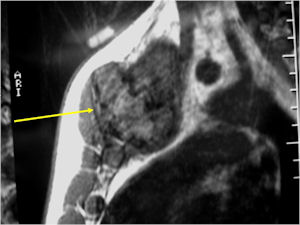

- Geographic, circumscribed lesion usually around 5cm in size.

- There may be expansion of bone, cortical thinning and cortical breakthrough. A soft tissue mass may accompany this lesion but the soft tissue component is usually contained by the periosteum.

- The periosteum remains intact around the soft tissue component. Might need a CT scan to detect the subtle calcification (Egg Shell Rim of Calcification) associated with an intact periosteal reaction

- The lesion may be entirely radiolucent but usually shows some degree of mineralization. Mineralization may appear stippled like cartilage but do not see chondroid pathologically. Mineralization is sometimes better detected on a CT scan rather than an x-ray.

CT Scan:

- More useful for detecting mineralization and evaluating extent of bone destruction than plain X-ray